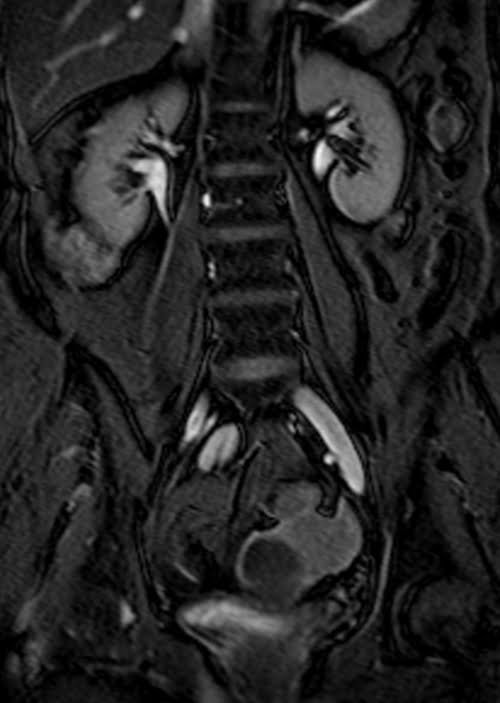

MRI kidney ureters and bladder( KUB) T2 TrueFISP fat saturated coronal images